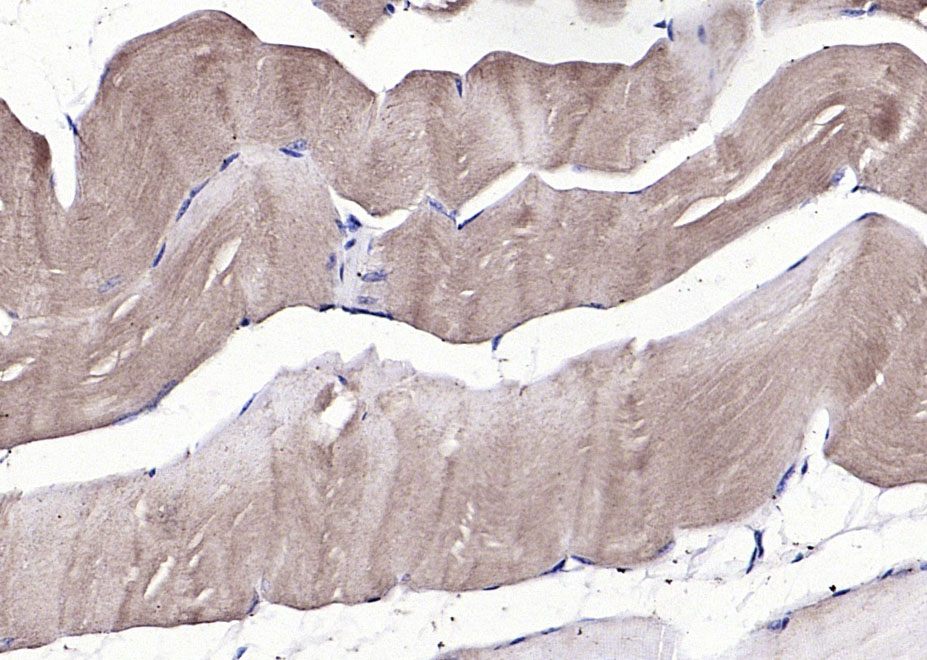

Paraformaldehyde-fixed, paraffin embedded (mouse skeletal muscle); Antigen retrieval by boiling in sodium citrate buffer (pH6.0) for 15min; Block endogenous peroxidase by 3% hydrogen peroxide for 20 minutes; Blocking buffer (normal goat serum) at 37°C for 30min; Antibody incubation with (Anti-GDF8) ) Polyclonal Antibody, Unconjugated (bs-23012R) at 1:200 overnight at 4°C, followed by operating according to SP Kit(Rabbit) (sp-0023) instructionsand DAB staining.

Paraformaldehyde-fixed, paraffin embedded (Rat tongue); Antigen retrieval by boiling in sodium citrate buffer (pH6.0) for 15min; Block endogenous peroxidase by 3% hydrogen peroxide for 20 minutes; Blocking buffer (normal goat serum) at 37°C for 30min; Antibody incubation with (Anti-GDF8) ) Polyclonal Antibody, Unconjugated (bs-23012R) at 1:200 overnight at 4°C, followed by operating according to SP Kit(Rabbit) (sp-0023) instructionsand DAB staining.

Paraformaldehyde-fixed, paraffin embedded (rat skeletal muscle); Antigen retrieval by boiling in sodium citrate buffer (pH6.0) for 15min; Block endogenous peroxidase by 3% hydrogen peroxide for 20 minutes; Blocking buffer (normal goat serum) at 37°C for 30min; Antibody incubation with (Anti-GDF8) ) Polyclonal Antibody, Unconjugated (bs-23012R) at 1:200 overnight at 4°C, followed by operating according to SP Kit(Rabbit) (sp-0023) instructionsand DAB staining.

Paraformaldehyde-fixed, paraffin embedded (rat stomach tissue); Antigen retrieval by boiling in sodium citrate buffer (pH6.0) for 15min; Block endogenous peroxidase by 3% hydrogen peroxide for 20 minutes; Blocking buffer (normal goat serum) at 37°C for 30min; Antibody incubation with (GDF8) Polyclonal Antibody, Unconjugated (bs-23012R) at 1:400 overnight at 4°C, followed by a conjugated secondary (sp-0023) for 20 minutes and DAB staining.